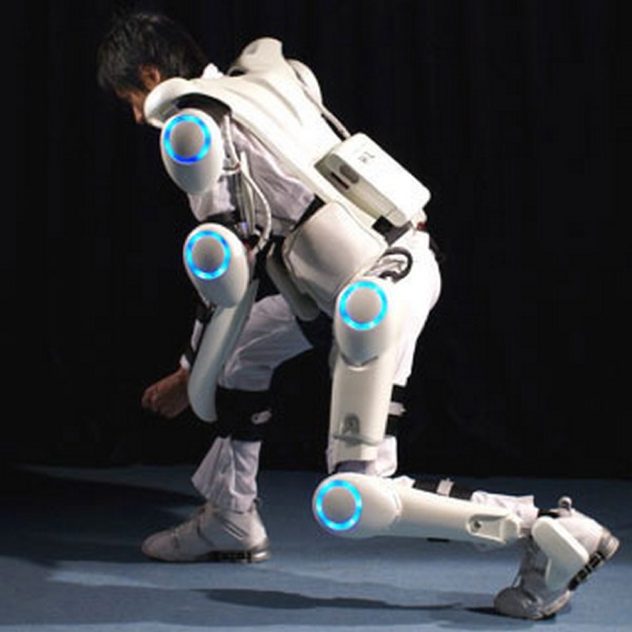

2. Bộ xương ngoài

Chúng ta không còn xa lạ với Iron Man nữa cho nên khái niệm Bộ xương ngoài đã trở nên gần gũi hơn. Một công ty sản xuất ở Mỹ đã tạo ra hàng trăm bộ giáp như vậy với hợp kim nhôm và titan để trợ giúp các bệnh nhân tê liệt, tổn thương tủy sống có thể đi bộ bình thường.

Công nghệ này cũng đã, đang được công ty Lockheed Martin ứng dụng đắc lực cho những người lính có thể mang vác trọng lượng tới 100kg và đi với tốc độ 16km/h trong thời gian dài. Trong tương lai gần, chúng ta sẽ được sở hữu những bộ giáp hữu dụng như vậy giá rẻ để khôi phục chức năng khi bị bại liệt hoặc tăng sức lao động, sức chịu đựng trong công việc nặng nhọc.